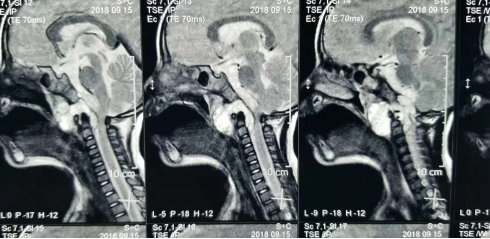

通常情况下,小孩子很少打鼾(俗称打呼噜),如果您的宝宝睡觉打鼾,并且声音很大,那要引起注意了,最好带孩子做个检查,因为睡觉打鼾也有可能是脑肿瘤引起的。